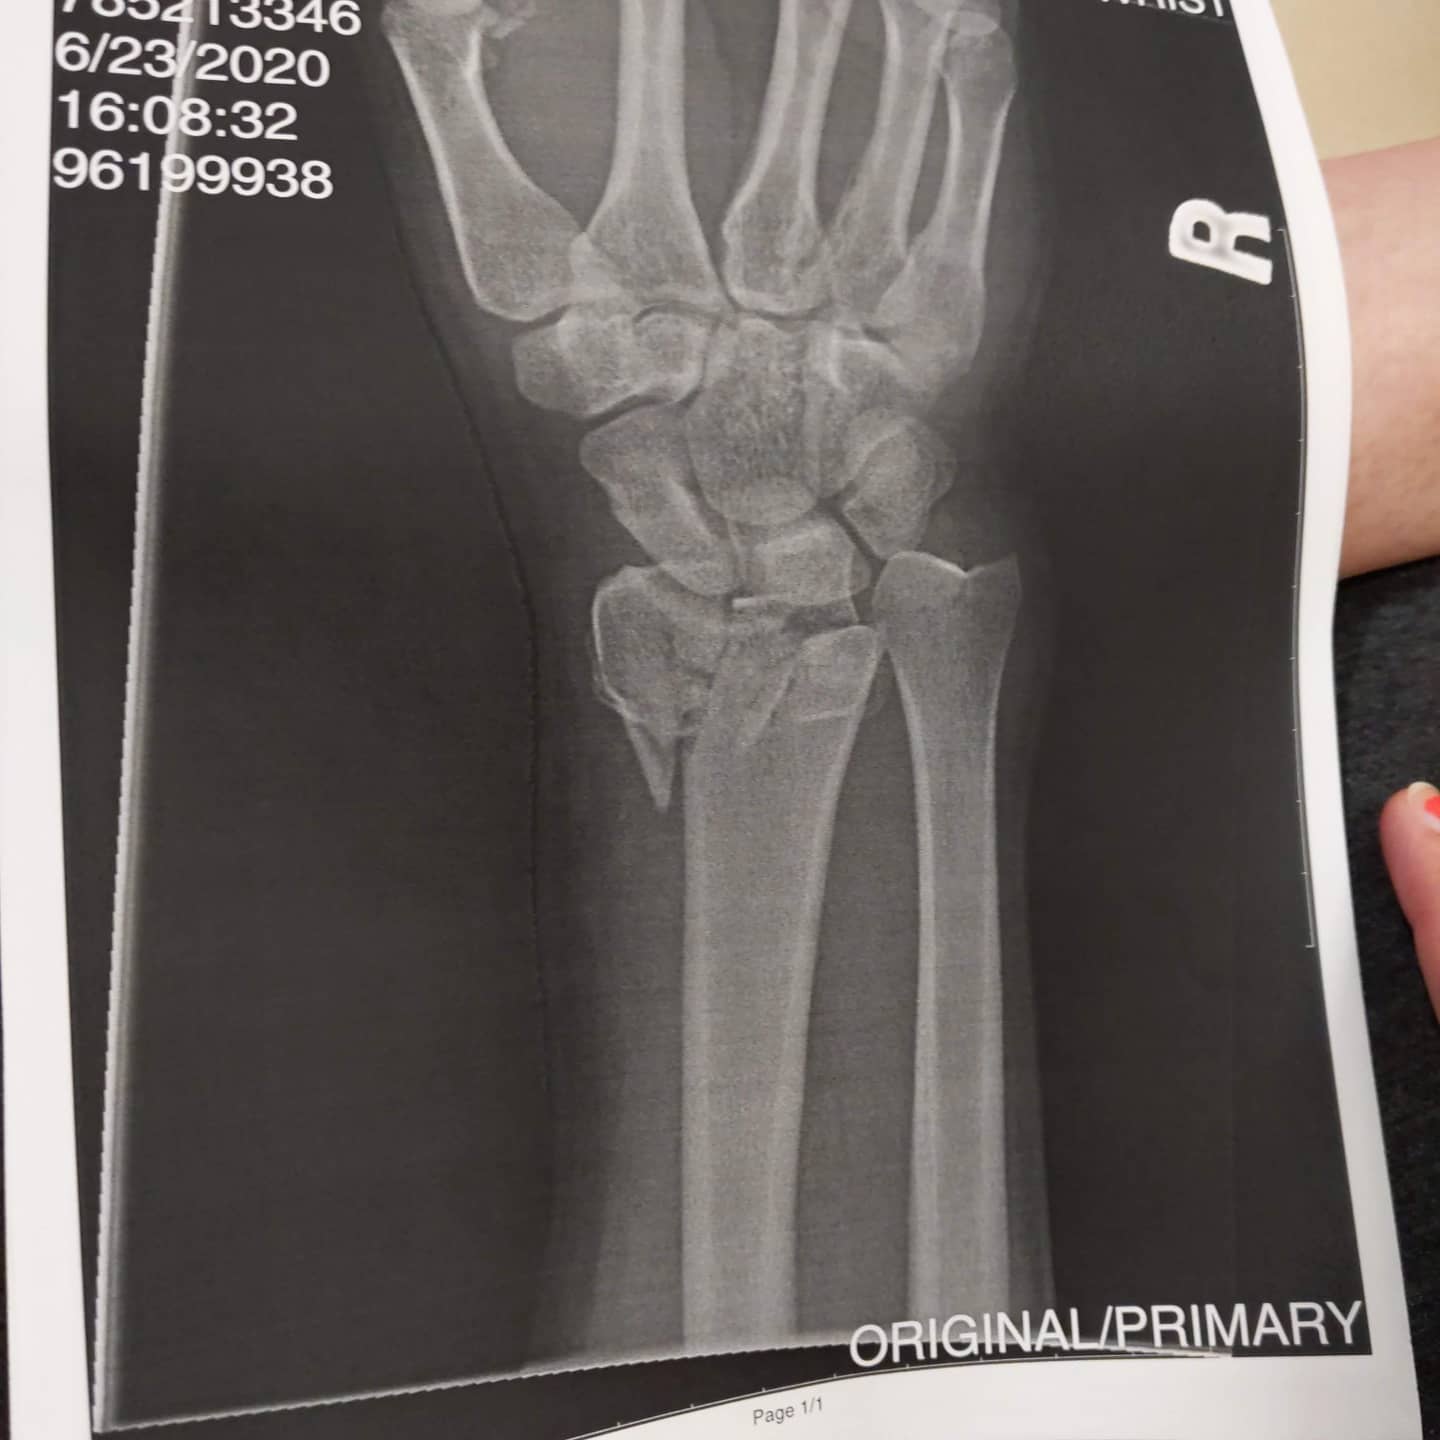

I was unloading several sheets of 3/4" Baltic Birch in May and it started raining so I started unloading faster. Instead of holding the sheets in front of me and walking down the grass hill to the basement entrance, I started walking backwards while sliding the wood on the grass.  This shouldn't matter because I was going to true up the factory edge. Anyways, I tripped over my retaining wall and fell backwards with my hand outstretched. I ended up with a compound fracture on my radius at the wrist and a broken ulna at the elbow. So my wife 7.5 months pregnant gets me to the local hospital....

We arrive and my forearm looks like a sine curve and the bone is sticking out the bottom. The triage doctor takes a look at me and says, this might be above our paygrade here so let's get you downtown to where the real carpenters are. They set the bone that night and, in the morning, I have surgery and get external fixators put in.

This recovery with the external fixators goes on for about 6 weeks, then they remove them and open up my wrist again and screw in some plates and put me in a cast. Summer is gone and we have our second kid!